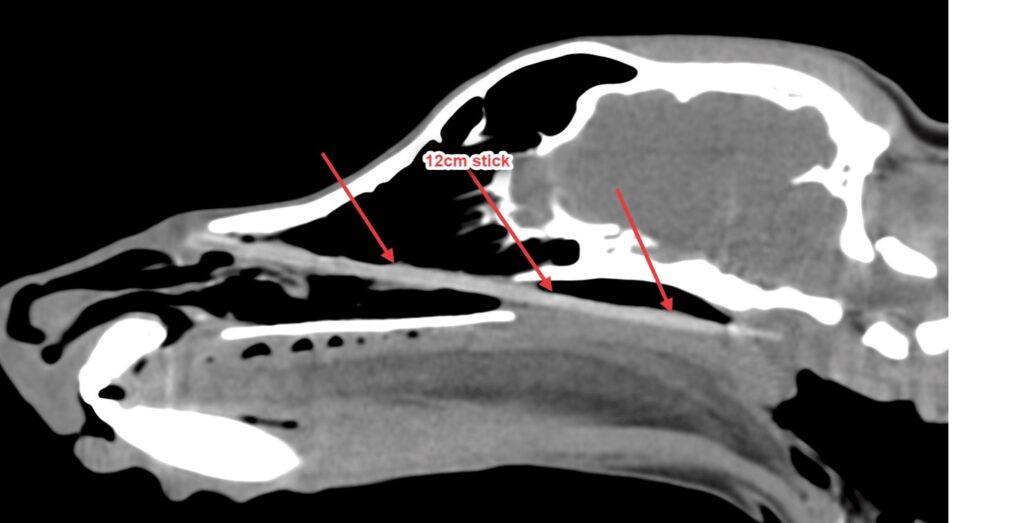

Esther recently surprised her family and the staff at Willows in Solihull when she underwent investigations for persistent sneezing and discomfort around her nose. A CT scan revealed a 12cm long stick in her nasal cavity which thankfully was able to be retrieved with the aid of rhinoscopy (a camera study of her nose). Quite how the stick managed to get stuck in this location remains a bit of a mystery!

CT scan carried out by Willows Imaging Team reveals a 12cm long stick in Esther’s nasal passage

The 12cm stick was almost the same size a ball point pen!